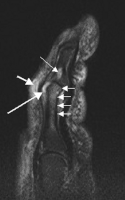

In psoriatic arthritis, pain can occur in the area of the sacrum (the lower back, above the tailbone),[3] as a result of sacroiliitis or spondylitis, which is present in 40% of cases. Pain can occur in and around the feet and ankles, especially enthesitis in the Achilles tendon (inflammation of the Achilles tendon where it inserts into the bone) or plantar fasciitis in the sole of the foot.[3]

Other symptoms that are more typical of psoriatic arthritis than other forms of arthritis include enthesitis (inflammation in the Achilles tendon (at the back of the heel) or the plantar fascia (bottom of the feet)), and dactylitis (sausage-like swelling of the fingers or toes).[10]

Enthesitis is observed in 30 to 50% of patients and most commonly involves the plantar fascia and Achilles’ tendon, but it may cause pain around the patella, iliac crest, epicondyles, and supraspinatus insertions[23]